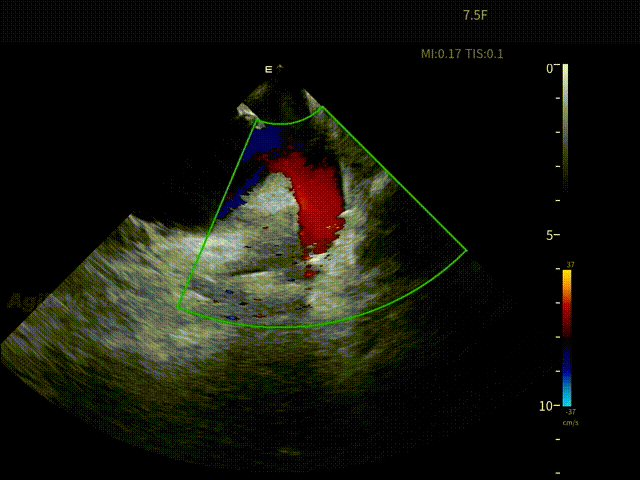

术中,基于AgileView™ 7.5Fr全球最细直径ICE导管的产品优势,周纬教授选择将ICE送入左房,以便更好地进行冷冻球囊的贴靠与位置的判断,在AgileView™ ICE实时影像的指导下, Arctic Front Advance Pro冷冻球囊导管消融导管安全进入左心房,先后完成双侧肺静脉隔离及顶部线隔离, ICE下可见导管贴靠良好,整个消融过程顺利,消融时间仅约25分钟,得益于超声设备清晰的成像质量,在顶部线隔离的时候可借助多普勒模式清晰的观察到球囊与组织的贴靠程度。 整个手术流程在ICE影像的指引下顺利完成,术中患者耐受良好,生命体征保持平稳。

ICE确认LSPV位置——C Mode

盐水判断封堵效果——有少量泄露

调整后无泄漏